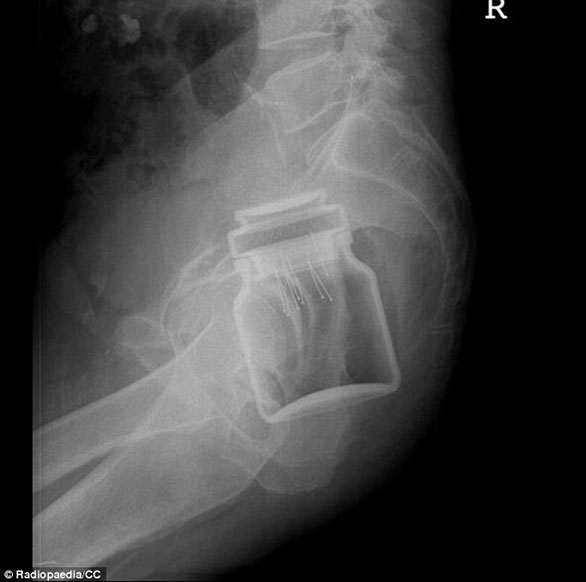

ضم الموقع مجموعة من الصور للأشعة السينية توضح أجساماً غريبة رُصدت داخل أجساد المرضى، ما أثارت دهشة الأطباء الذين قرروا رفعها على موقع طبي متخصص كمادة تعليمية ومرجعية بحثية واستشارية للدارسين في كليات الطب، والذي أنشئ من قبل طبيب أشعة أسترالي عام 2005، بحسب صحيفة دايلي ميل البريطانية.

صورة لأشعة "إكس راي" لمريض دخل معدته برطمان قهوة.